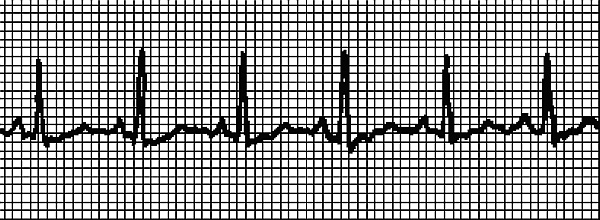

На рис. 4 записана несинусовая тахикардия. Водитель ритма смещен в предсердие. Если такая тахикардия легко устранится, то причина может быть не связана с болезнью сердца.

Врач иногда снимает подобное состояние массажем! Это так называемый массаж каротидного синуса, который проводится в области сонной артерии (καρόω и означает «засыпать», по-гречески). Но без диагностики состояния, без ЭКГ «назначить» массаж нельзя, он не является безобидной процедурой и может нанести вред! Поэтому при пароксизмальной тахикардии ограничимся рекомендацией надавливать на глазные яблоки , которую мы уже приводили. При устойчивой предсердной аритмии можно заподозрить легочную недостаточность или инфаркт миокарда.

Рис. 4. Несинусовая тахикардия